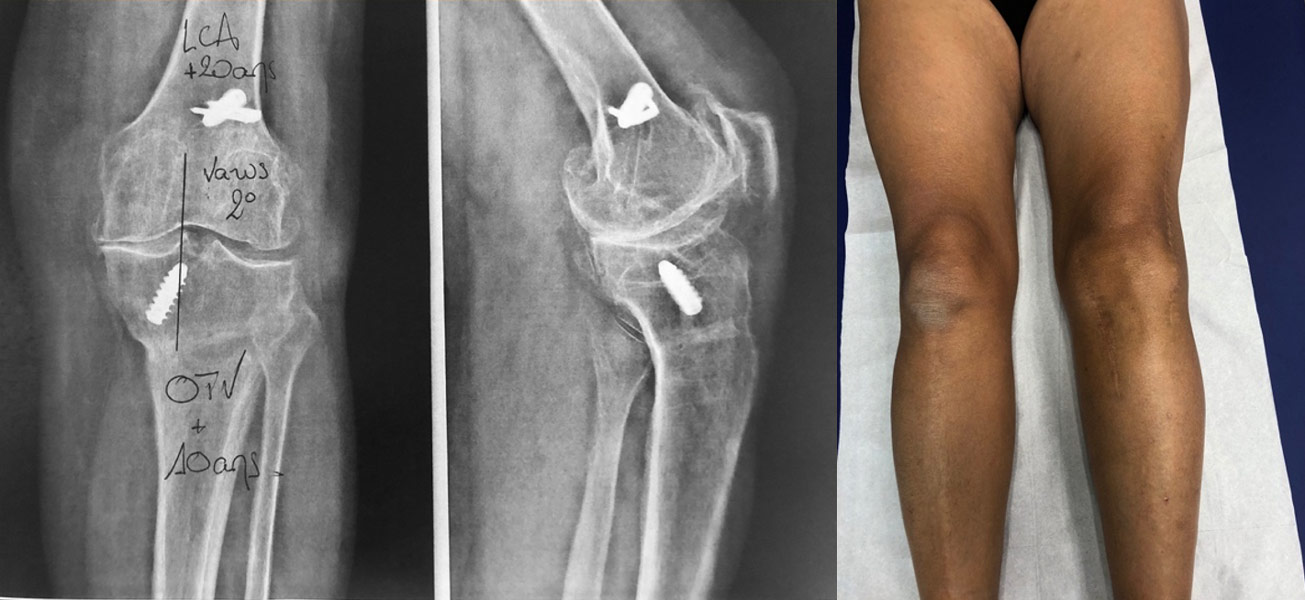

Déformation du genou en valgus (jambes en X), femme jeune (45 ans), ancienne handballeuse aux jeux de Séoul ; le fémur et le tibia sont déformés. Handicap majeur.

On réalise une double ostéotomie de varisation lors de la même opération, fémorale et tibiale, fixées avec des agrafes métalliques.

10 ans après l’ostéotomie, excellent résultat : aucune douleur, mobilités normales.